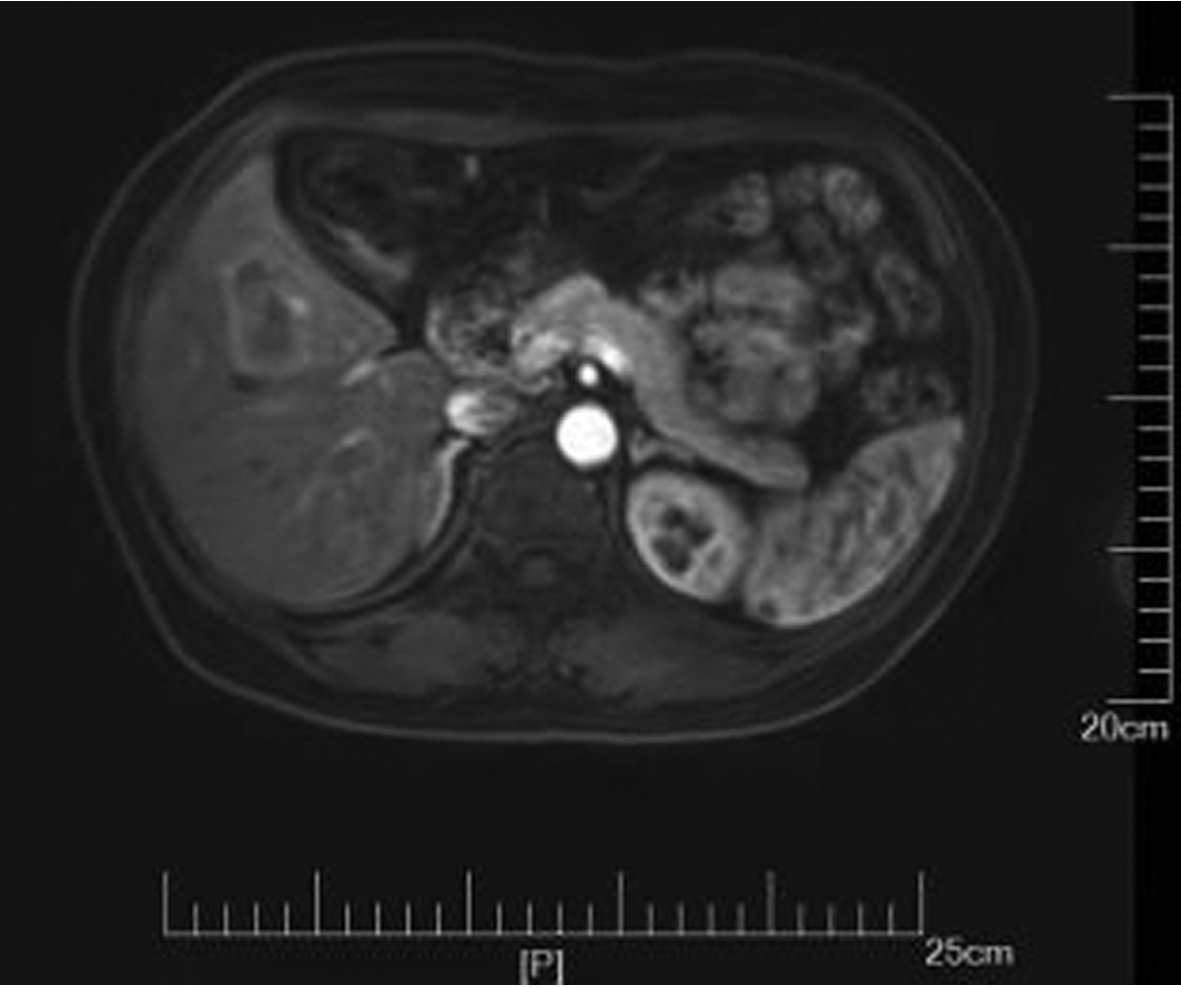

IgG4-related retroperitoneal fibrosis: A case report

2022, 38(5): 1126-1128. DOI: 10.3969/j.issn.1001-5256.2022.05.030

Abstract: